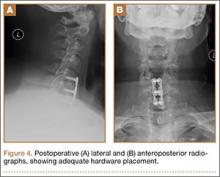

A 54-year-old man with a body mass index (BMI) of 50 presented with neck and bilateral arm pain, with left greater than right radicular symptoms in the C6 and C7 distribution. Magnetic resonance imaging (MRI) showed disc herniations at C5-C6 and C6-C7 with spinal cord signal changes, and he underwent a C5-C6 and C6-C7 anterior cervical discectomy and fusion. Initial localization was determined using a lateral radiograph and vertebral needle. During hardware placement, anteroposterior and lateral fluoroscopic radiographs confirmed adequate placement of the superior screw, but visualization of the inferior portion of the plate and inferior screw was challenging (Figure 2). Our oblique 30º–30º view provided better visualization of the plate and screws in the lower cervical vertebrae than lateral imaging, and allowed confirmation that the hardware was positioned correctly (Figure 3). It took 1 attempt to achieve adequate visualization with the 30º–30º view.

Postoperatively, the patient’s radiculopathy and motor weakness improved. Radiographs confirmed adequate hardware placement, and he was discharged on postoperative day 1 (Figure 4). Imaging at the patient’s 6-week follow-up confirmed adequate fusion from C5-C7, anatomically aligned facet joints, and no hardware failure. The patient’s Neck Disability Index was 31/50 preoperatively and 26/50 at this visit.